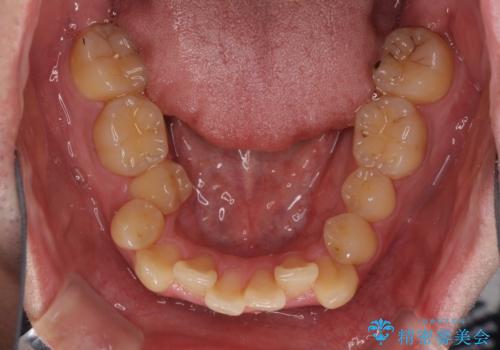

- 上下のデコボコと前歯のクロスバイトを改善したいとのことで来院された患者様です。

マウスピース矯正での自己管理には自信がないとのことで、ワイヤー装置による矯正治療を行うこととしました。

デコボコの程度は強かったのですが、口元の突出感はなかったため、非抜歯矯正としました。